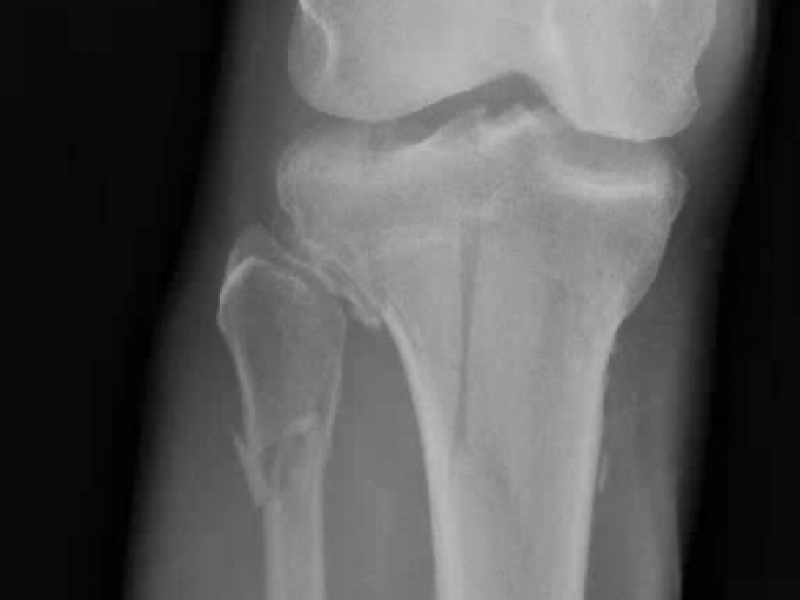

What's the Diagnosis? By Dr. Loran Hatch

A 55 yo M presents to the ED after being struck by a motor